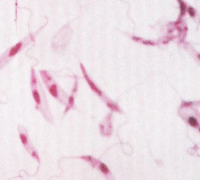

ブラジルリーシュマニア ~ 中南米の森林に生息するげっ歯類、ナマケモノ、サルの皮膚のリーシュマニア症の原因虫

ブラジルリーシュマニア:リーシュマニア・ブラジリエンシス(Leishmania braziliensis)中南米の森林に生息するげっ歯類、ナマケモノ、サルの皮膚のリーシュマニア症の原因虫ですが、しばしばヒトの鼻咽頭に病変を生ずることがありま...